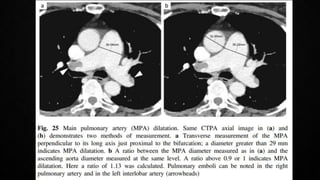

COMPUTERISED TOMOGRAPHIC PULMONARY

ANGIOGRAPHY (CTPA)

• Multidetector CTPA is the method of choice for imaging the pulmonary vasculature in

suspected PE

• PIOPED II Study (Prospective Investigation On Pulmonary Embolism Diagnosis)

observed a sensitivity of 83% and a specificity of 96%

• In patient with a low/intermediate pre-test probability, negative predictive value of a

CTPA to rule out PE was high (96%/89%), but only 60% if the pre-test probability was

high

• The positive predictive value is high (92-96%) if the pre-test probability is intermediate or

high, but much lower (58%) if the clinical likelihood was low

• Remains controversial whether patients with a negative CTPA and a high clinical

probability should be further investigated

• Pre-existing CTEPH should not be missed

COMPUTERISED TOMOGRAPHIC PULMONARY ANGIOGRAPHY(CTPA) • Multidetector CTPA is the method of choice for imaging the pulmonary vasculature in suspected PE • PIOPED II Study (Prospective Investigation On Pulmonary Embolism Diagnosis) observed a sensitivity of 83% and a specificity of 96% • In patient with a low/intermediate pre-test probability, negative predictive value of a CTPA to rule out PE was high (96%/89%), but only 60% if the pre-test probability was high • The positive predictive value is high (92-96%) if the pre-test probability is intermediate or high, but much lower (58%) if the clinical likelihood was low • Remains controversial whether patients with a negative CTPA and a high clinical probability should be further investigated • Pre-existing CTEPH should not be missed